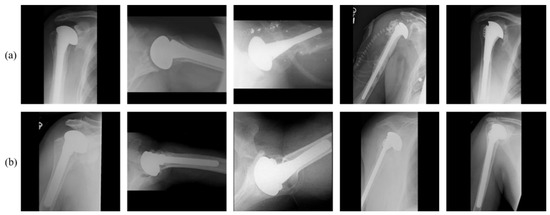

4.1. Dataset and Experimental Setups